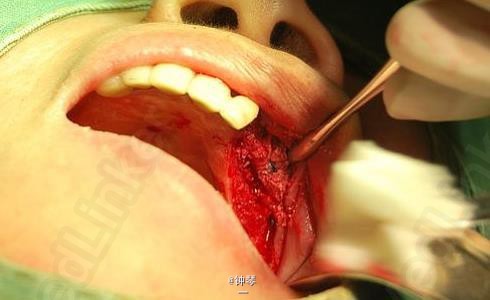

刀刃状牙槽嵴种植+钛网应用

左上3、4、6种植